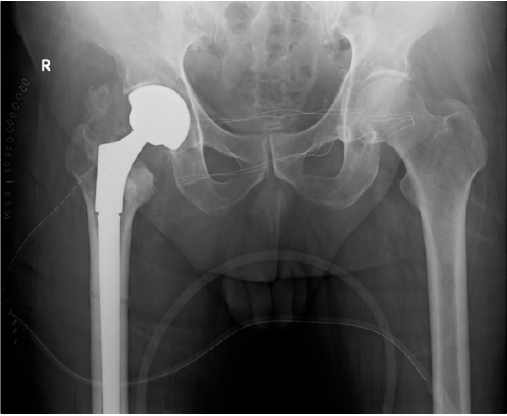

The patient was a 68 years old male, who had a car accident (Table 1). When he was admitted to the hospital, X-ray examination revealed a fracture of the surgical neck of left humerus and a fracture of the right femoral neck. He was treated with an intramedullary nailing of the femur (Proximal Femoral Nail Antirotation - PFNA system by ©DePuy Synthes) (Figure 1). The humerus fracture was managed conservatively with a shoulder immobilization for the first two weeks. The patient had an uneventful postoperative period, and he began immediately postoperative rehabilitation without weight bearing for the first two weeks. He continued his rehabilitation program in the following months, after hospital discharge, in a physiotherapy centre near his home. He placed on him from the third week, and two weeks later he has recovered to walk by himself, with the help of two crutches. At 6 months of follow-up, the Physicians (M.P., D.L.) noted a delayed healing of the fractures on X-ray (Figure 2), despite the good clinical condition of the patient, in fact he had no pain, and he was able to walk by himself without crutches or a limp. In addition, the patient missed the one-year follow-up due to pandemic emergency in March 2020. Two months after, he developed groin pain of the right hip and it was treated with a phone consultation by his general practitioner for a sciatic problem. Because of the persistent pain he called his surgeon who prescribed a new X-ray that revealed a superomedial migration of the proximal femoral blade, a phenomenon called cutin [12] (Figures 3 & 4). For this reason, the patient underwent a primary total hip arthroplasty with stem revision (©Lima Corporate) in October 2020 (Figure 5).

Figure 5: X-ray postoperative control.